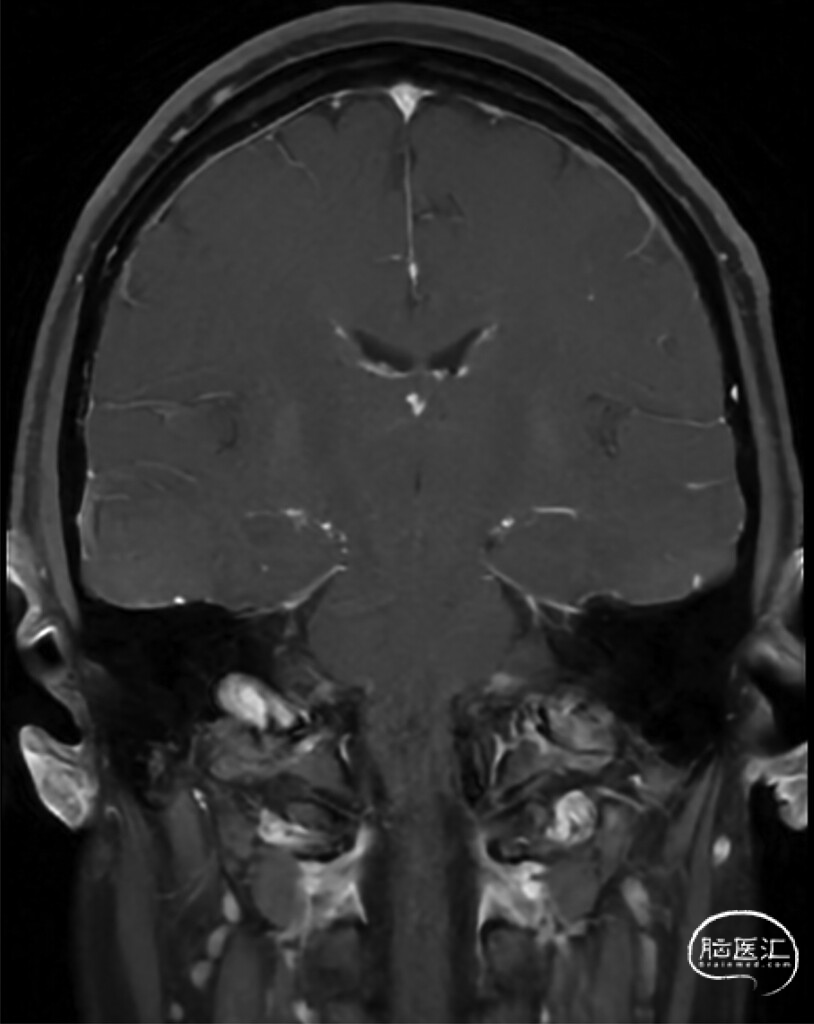

● 首次头颅非增强MRI显示符合颅内低压的影像学表现(图1)。因患者当时妊娠34周,暂缓CTM检查,由麻醉科医师在无影像引导下为其实施了非靶向腰椎硬膜外血贴治疗,术后症状完全缓解。6个月后,患者因症状复发再次就诊。复查增强头颅MRI仍提示颅内低压表现,并新增硬脑膜弥漫性强化(图2)。全脊柱MRI显示腹侧硬膜外脑脊液信号积聚,高度提示1型脑脊液漏(图3)。CTM证实存在T4至T11节段腹侧硬膜外造影剂积聚,但未能明确漏口位置。

图2:症状复发6个月后复查T1加权脂肪抑制增强头颅MRI,显示硬脑膜弥漫性强化。